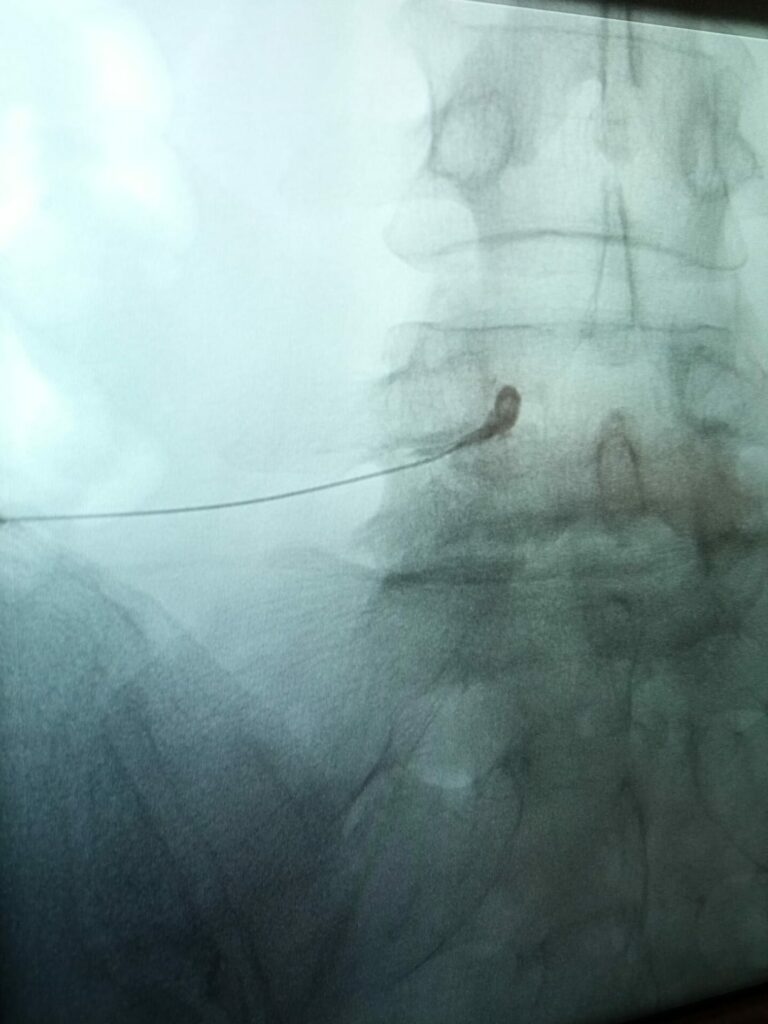

Więcej rzetelnych informacji na temat iniekcji nadtwardówkowych prezentujemy tutaj.